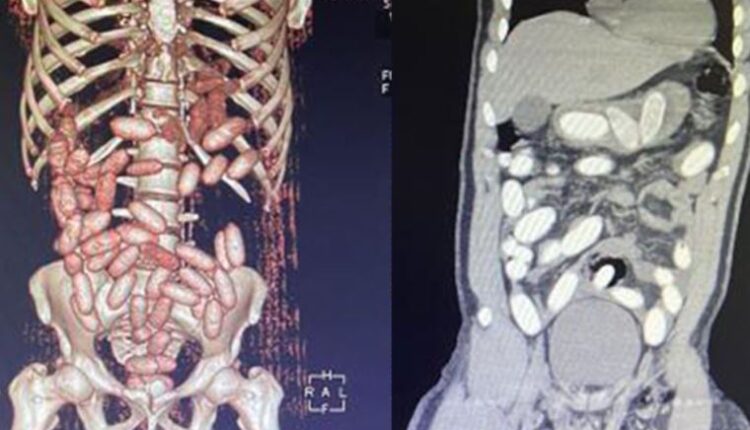

Gümrük Muhafaza ekiplerince savcılık talimatı doğrultusunda detaylı bilgisayar tomografi çekilmesi için sağlık kuruluşuna götürülen 6 yolcunun yapılan tarama ve muayenelerinde 761 adet ve toplam ağırlığı 10 kilo 420 gram kokain tespit edildi.

İkinci operasyonda, başka yolcunun da ‘yutucu’ kurye olduğu bilgisine ulaşan ekipler, şüpheliyi takibe aldı. Yolcuda, ‘yutucu’ tespit cihazı ve ardından sağlık kuruluşunda yapılan muayene sonucu 48 adet kapsül ve toplam ağırlığı 760 gram kokain ele geçirildi. Ayrıca yakalanan şüphelileri Türkiye’de karşılayacak Nijerya uyruklu da kaldığı otelde gözaltına alındı. Operasyonlarda toplamda 11 kilo 180 gram kokain ele geçirildi ve 1’i organizatör, 7’si kurye olmak üzere 8 kişi gözaltına alındı. Şüpheliler, sevk edildiği adliyede çıkarıldığı hakimlikçe tutuklanarak, cezaevine gönderildi.